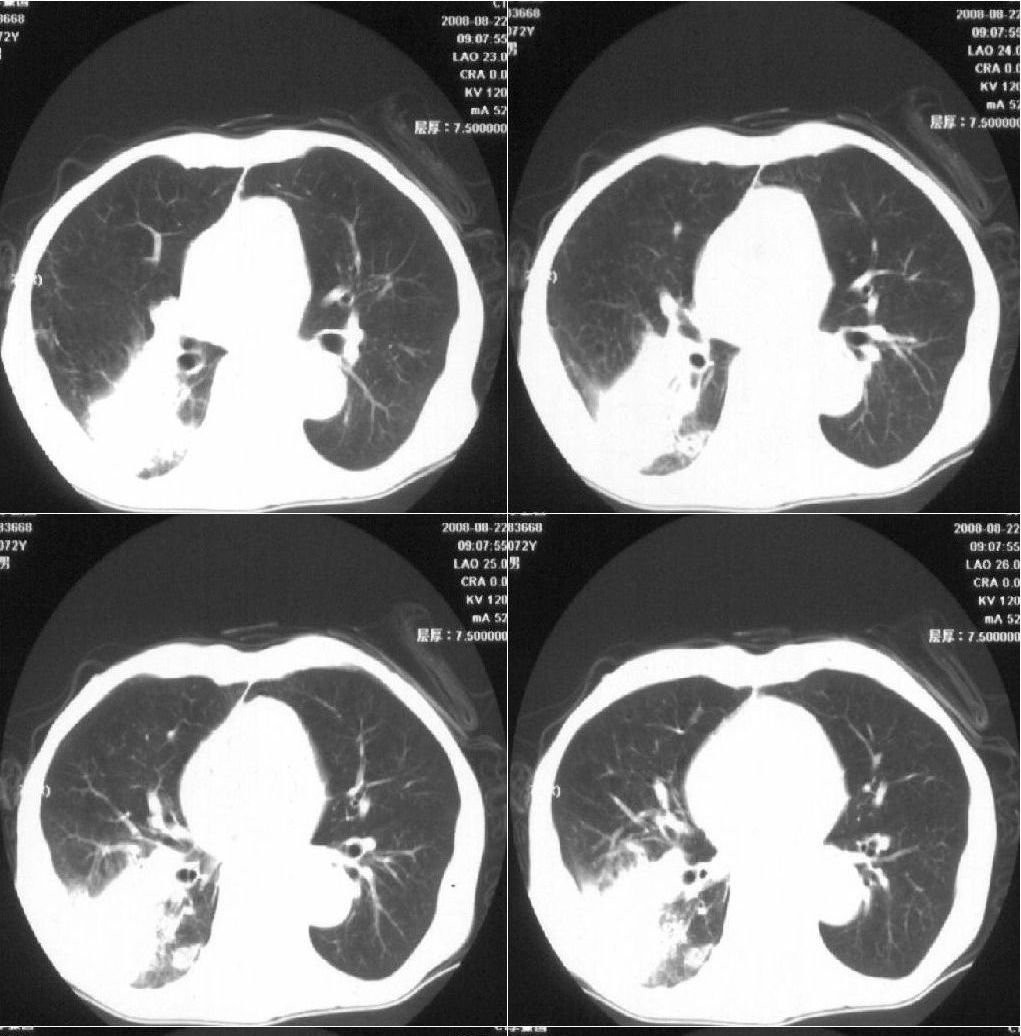

标题: CT15789:男性,72岁。食管癌术后14年。 [打印本页]

标题: CT15789:男性,72岁。食管癌术后14年。

痰培养:见葡萄球菌,霉菌少量生长。(此片系外院所作,仅提供了增强后的ct值为100hu,中心的坏死部分无强化,患者现在身体状况欠佳,为恶液质状态)

考虑肺癌可能性大伴阻塞性炎症

周围型肺癌可能性大.

考虑右肺下叶感染性病变(肺脓肿?);建议抗炎治疗后复查。

病人无发热,消瘦,考虑ca

考虑右下肺慢性感染性病变

符合机遇性感染,真菌可能性大。